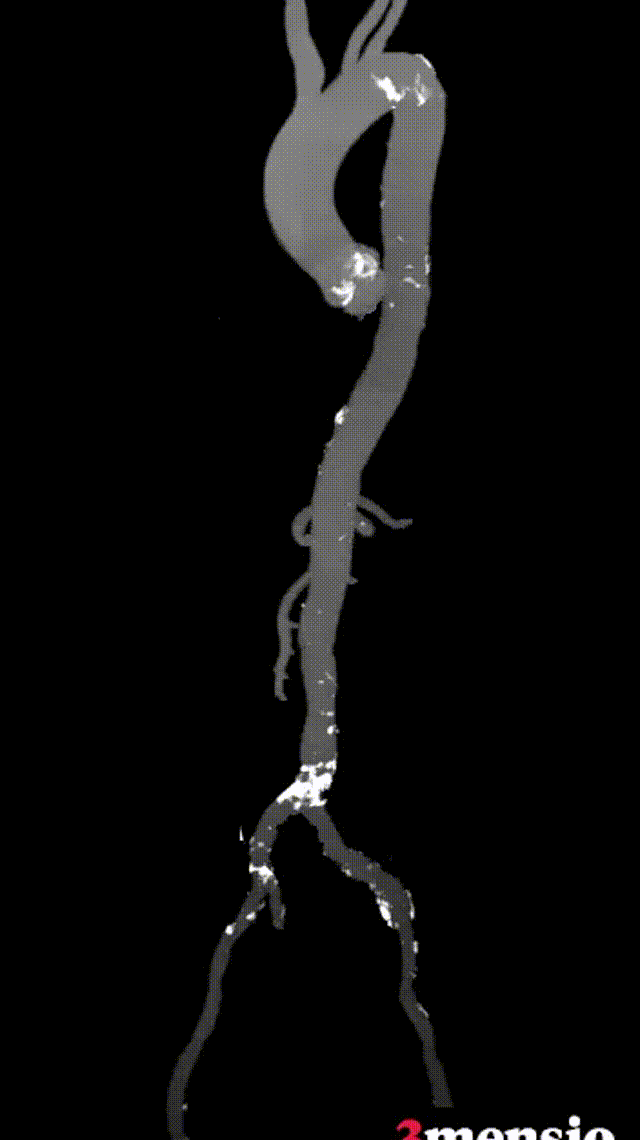

1.根据术前测量分析,采取右侧股动脉作为主入路,左股为辅入路,置入猪尾进行根部造影,造影可见主动脉根部瓣叶活动度低,冠脉灌注良好,少-中量反流。

根部造影